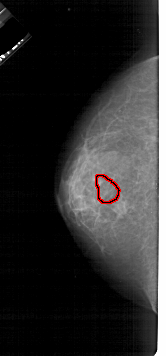

A_1931_1.LEFT_MLO

LEFT_MLO LINES 5446 PIXELS_PER_LINE 2491 BITS_PER_PIXEL 12 RESOLUTION 43.5 OVERLAY

FILE: A_1931_1.LEFT_MLO.OVERLAY

TOTAL_ABNORMALITIES 1

ABNORMALITY 1

LESION_TYPE MASS SHAPE IRREGULAR MARGINS ILL_DEFINED

ASSESSMENT 4

SUBTLETY 4

PATHOLOGY MALIGNANT

TOTAL_OUTLINES 1

BOUNDARY